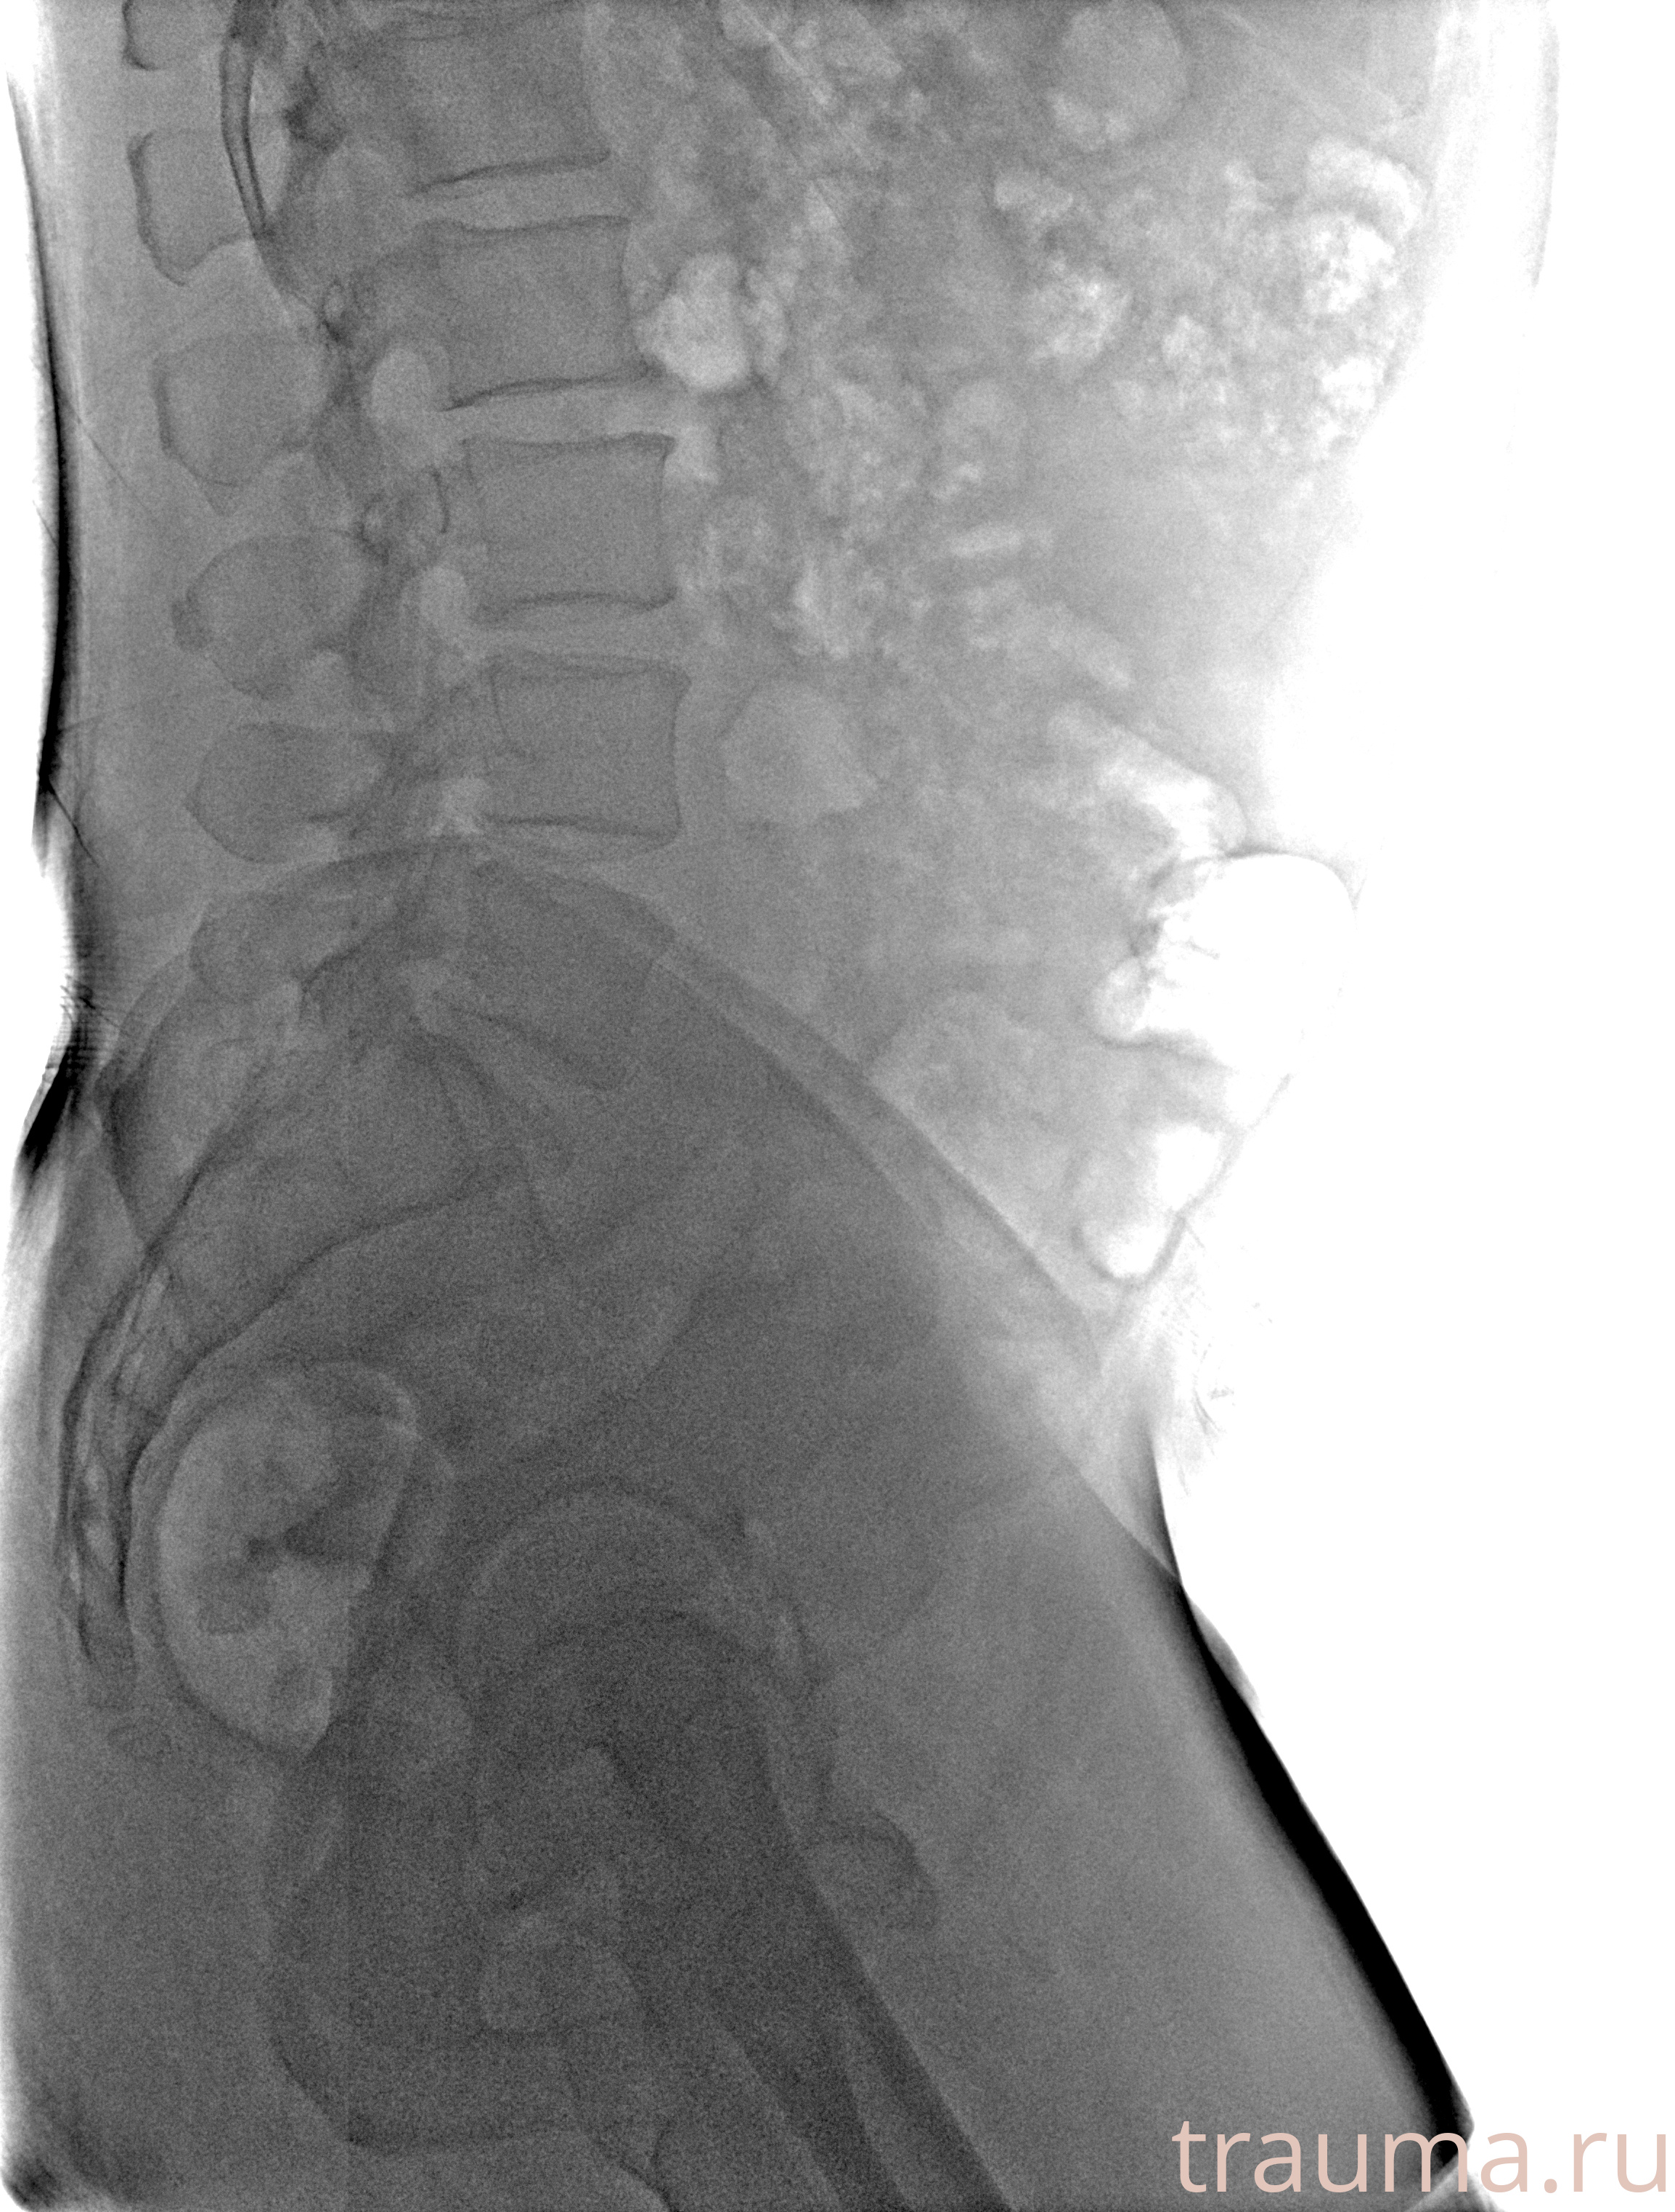

Рентгенограммы

Рентген на дому: по вашему адресу приезжает врач-рентгенолог, травматолог-ортопед с мобильным рентгеновским аппаратом, проводит диагностику травмы или заболевания, делает необходимые рентгенограммы, дает рекомендации по дальнейшему лечению. Получить качественные снимки в домашних условиях возможно благодаря уникальной методике, разработанной МосРентген Центром для института  Склифосовского